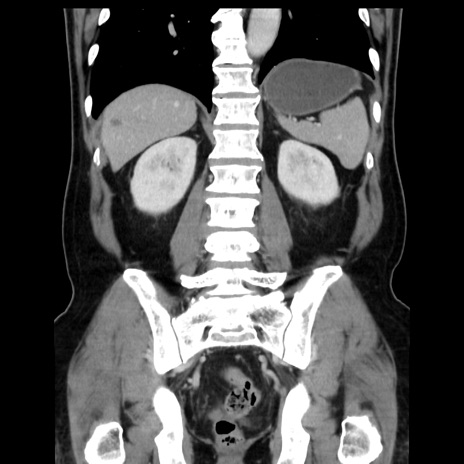

症例16(冠状断像)

【症例】 70歳代男性

【主訴】 腹痛、嘔吐

【現病歴】 約1ヶ月前より間欠的に腹痛と嘔吐あり、当院消化器内科を受診したところCTで多発する肝臓のLDAを指摘され、精査中であった。以降は消化器症状は安定していたが、2日前より嘔気と腹痛があり、同日より排便・排ガスが消失した。改善認めず、 本日、救急外来を受診した。

【既往歴】 大腸ポリープ切除後。

【身体所見】意識清明・会話良好、BT 36.3℃、BP 127/80mmHg、 P 80bpm、腹部:膨満あり、平坦・軟、上腹部正中および下腹部正中に圧痛あり、反跳痛なし、筋性防御なし。

【データ】WBC 7200、CRP 0.77